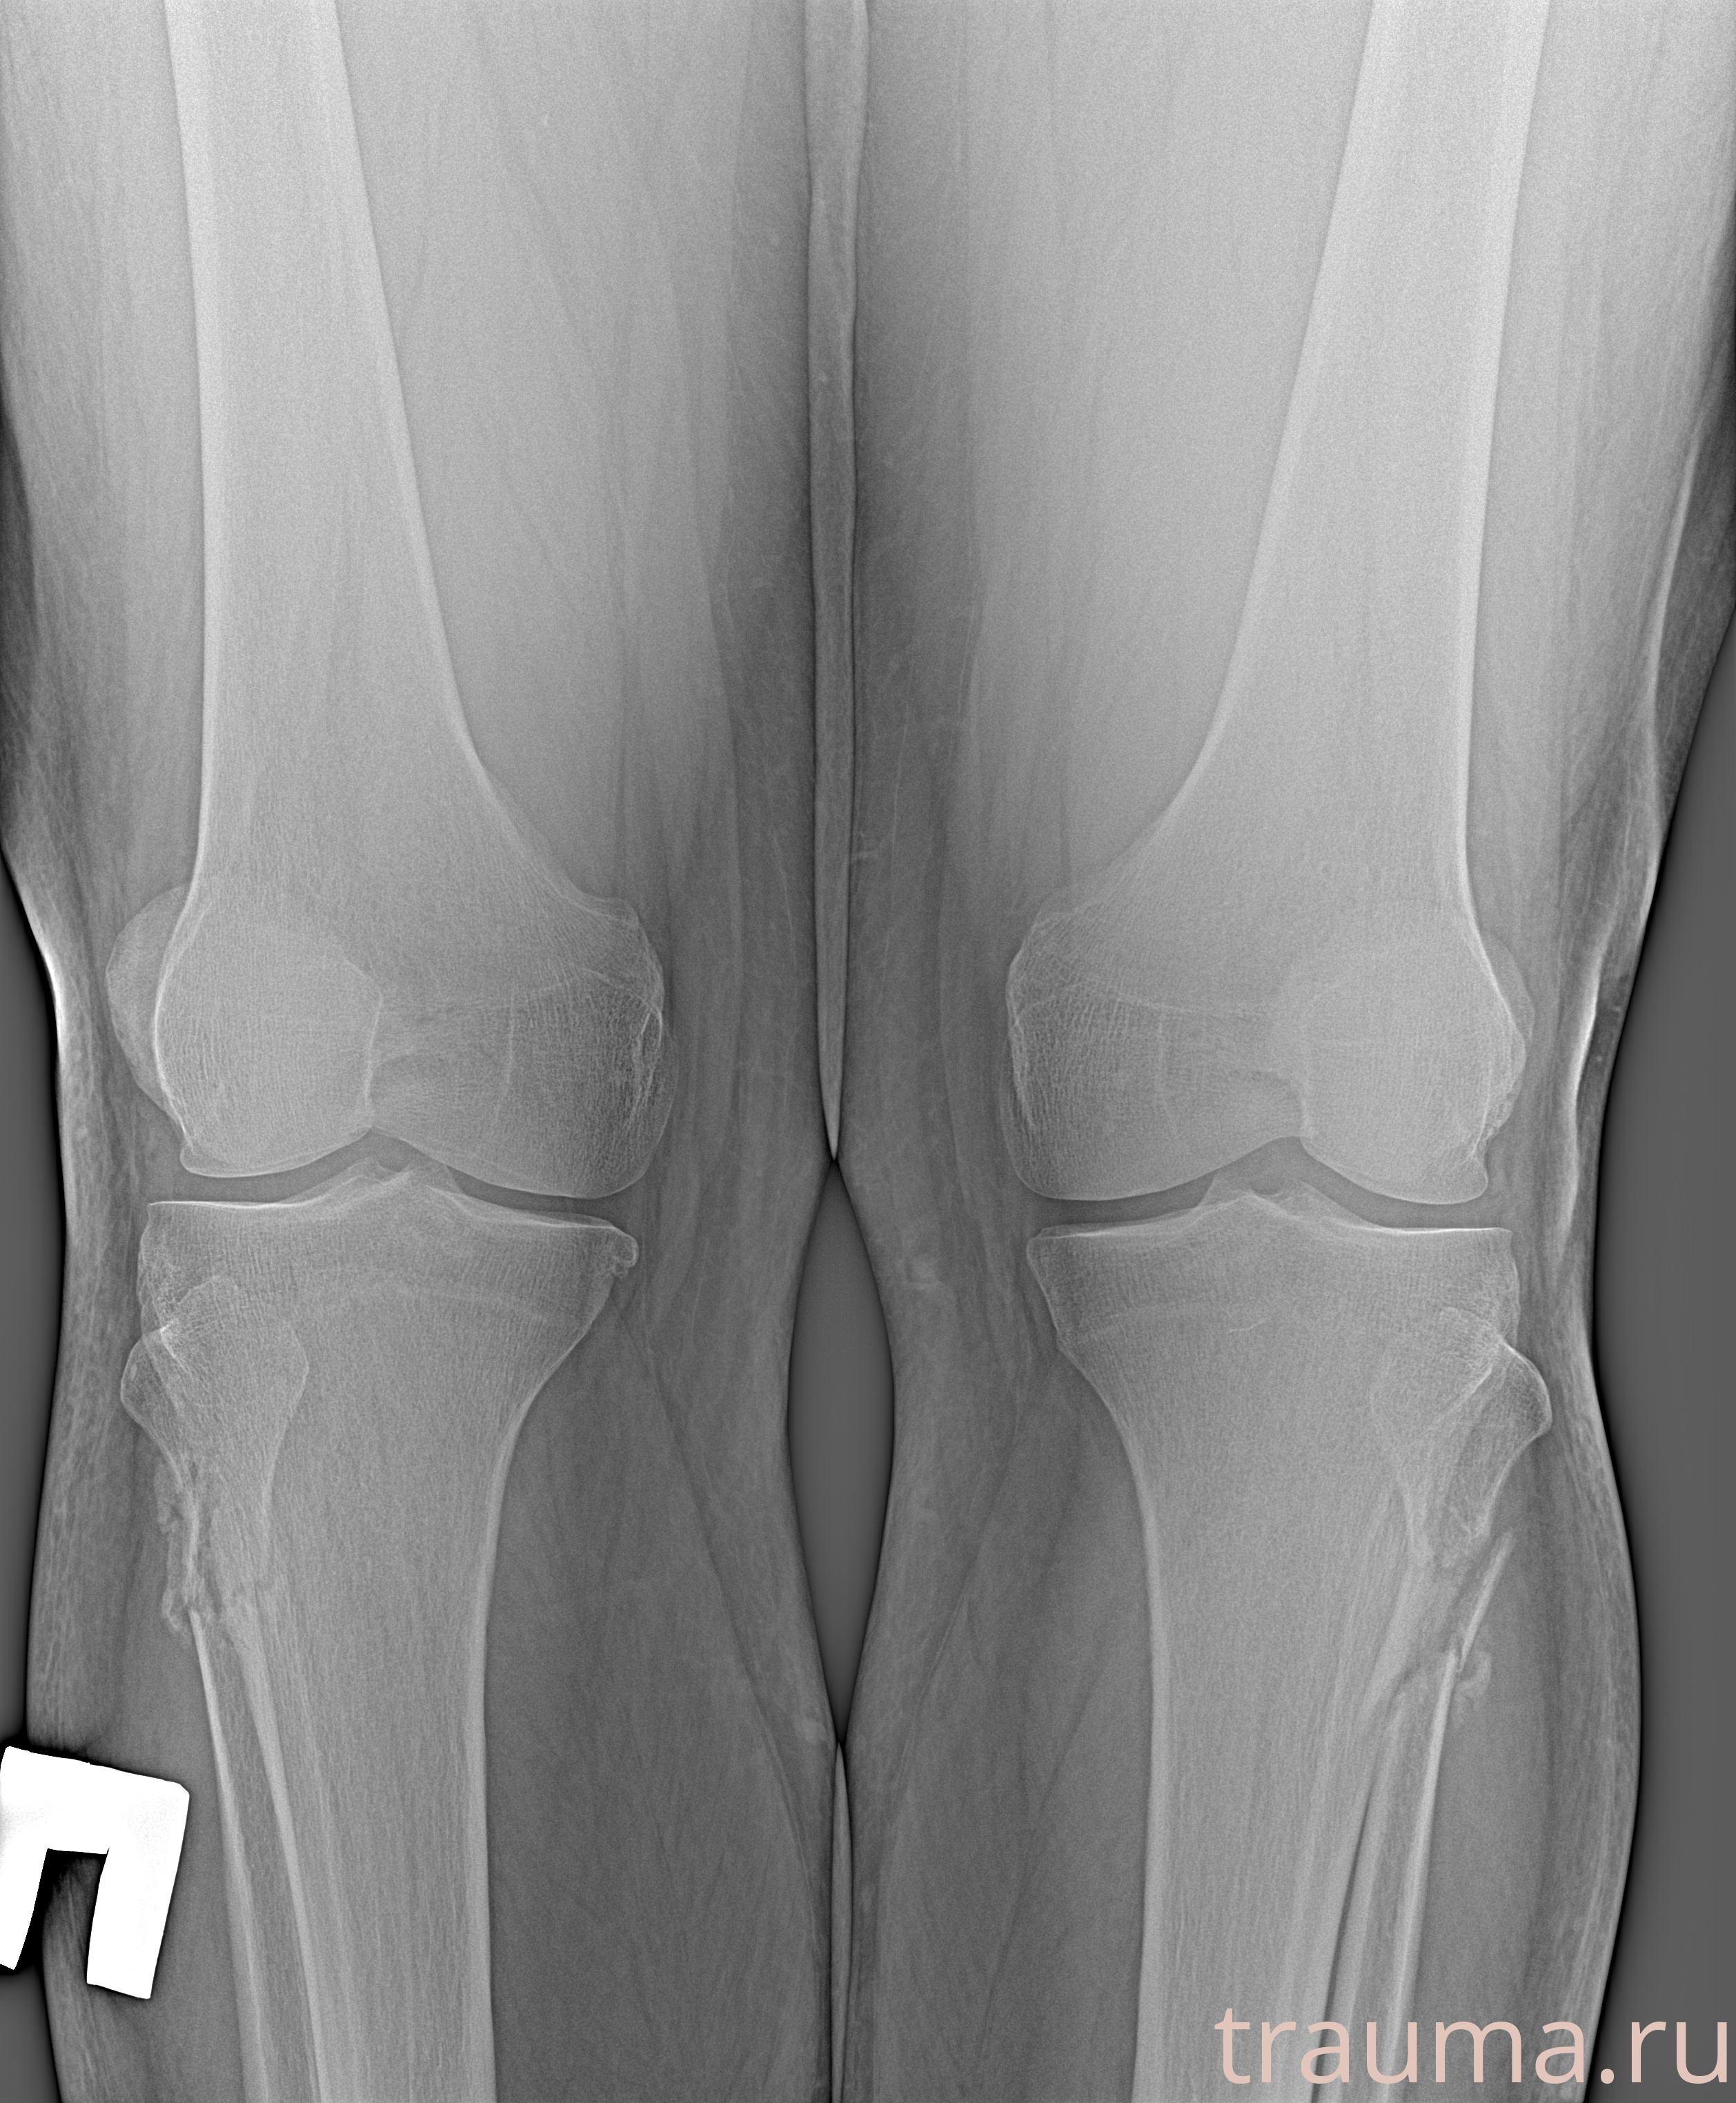

Рентгенограммы

Рентген на дому: по вашему адресу приезжает врач-рентгенолог, травматолог-ортопед с мобильным рентгеновским аппаратом, проводит диагностику травмы или заболевания, делает необходимые рентгенограммы, дает рекомендации по дальнейшему лечению. Получить качественные снимки в домашних условиях возможно благодаря уникальной методике, разработанной МосРентген Центром для института  Склифосовского